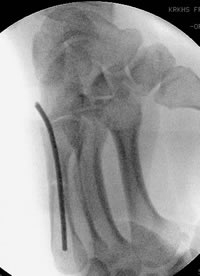

läßt sich leicht mit der retrograden Nagelung verwirklichen. Dabei wird an der Basis des MHK mit dem Pfriem der Markraum eröffnet. Danach weirden ein oder zwei 1.8 mm oder 2 mm starke Kirschnerdrähte eingebracht. Die Drähte werden mit dem stumpfen Ende, das leicht gebogen wird, eingeschoben. Die scharfe Spitze wird abgekniffen und der Draht in ein Jacobsfutter eingespannt. Mit der gebogenen Spitze läßt sich die Fraktur durch Drehen des Drahtes reponieren.

Stabilisierung der MHK Schaftfraktur. Übungsstabilität und freie Funktion der Hand sind postoperativ möglich.

Selbst eine basisnahe Fraktur läßt sich sofort und übungsstabil versorgen. Die Operation wird ambulant in iV-Lokalanästesie durchgeführt.